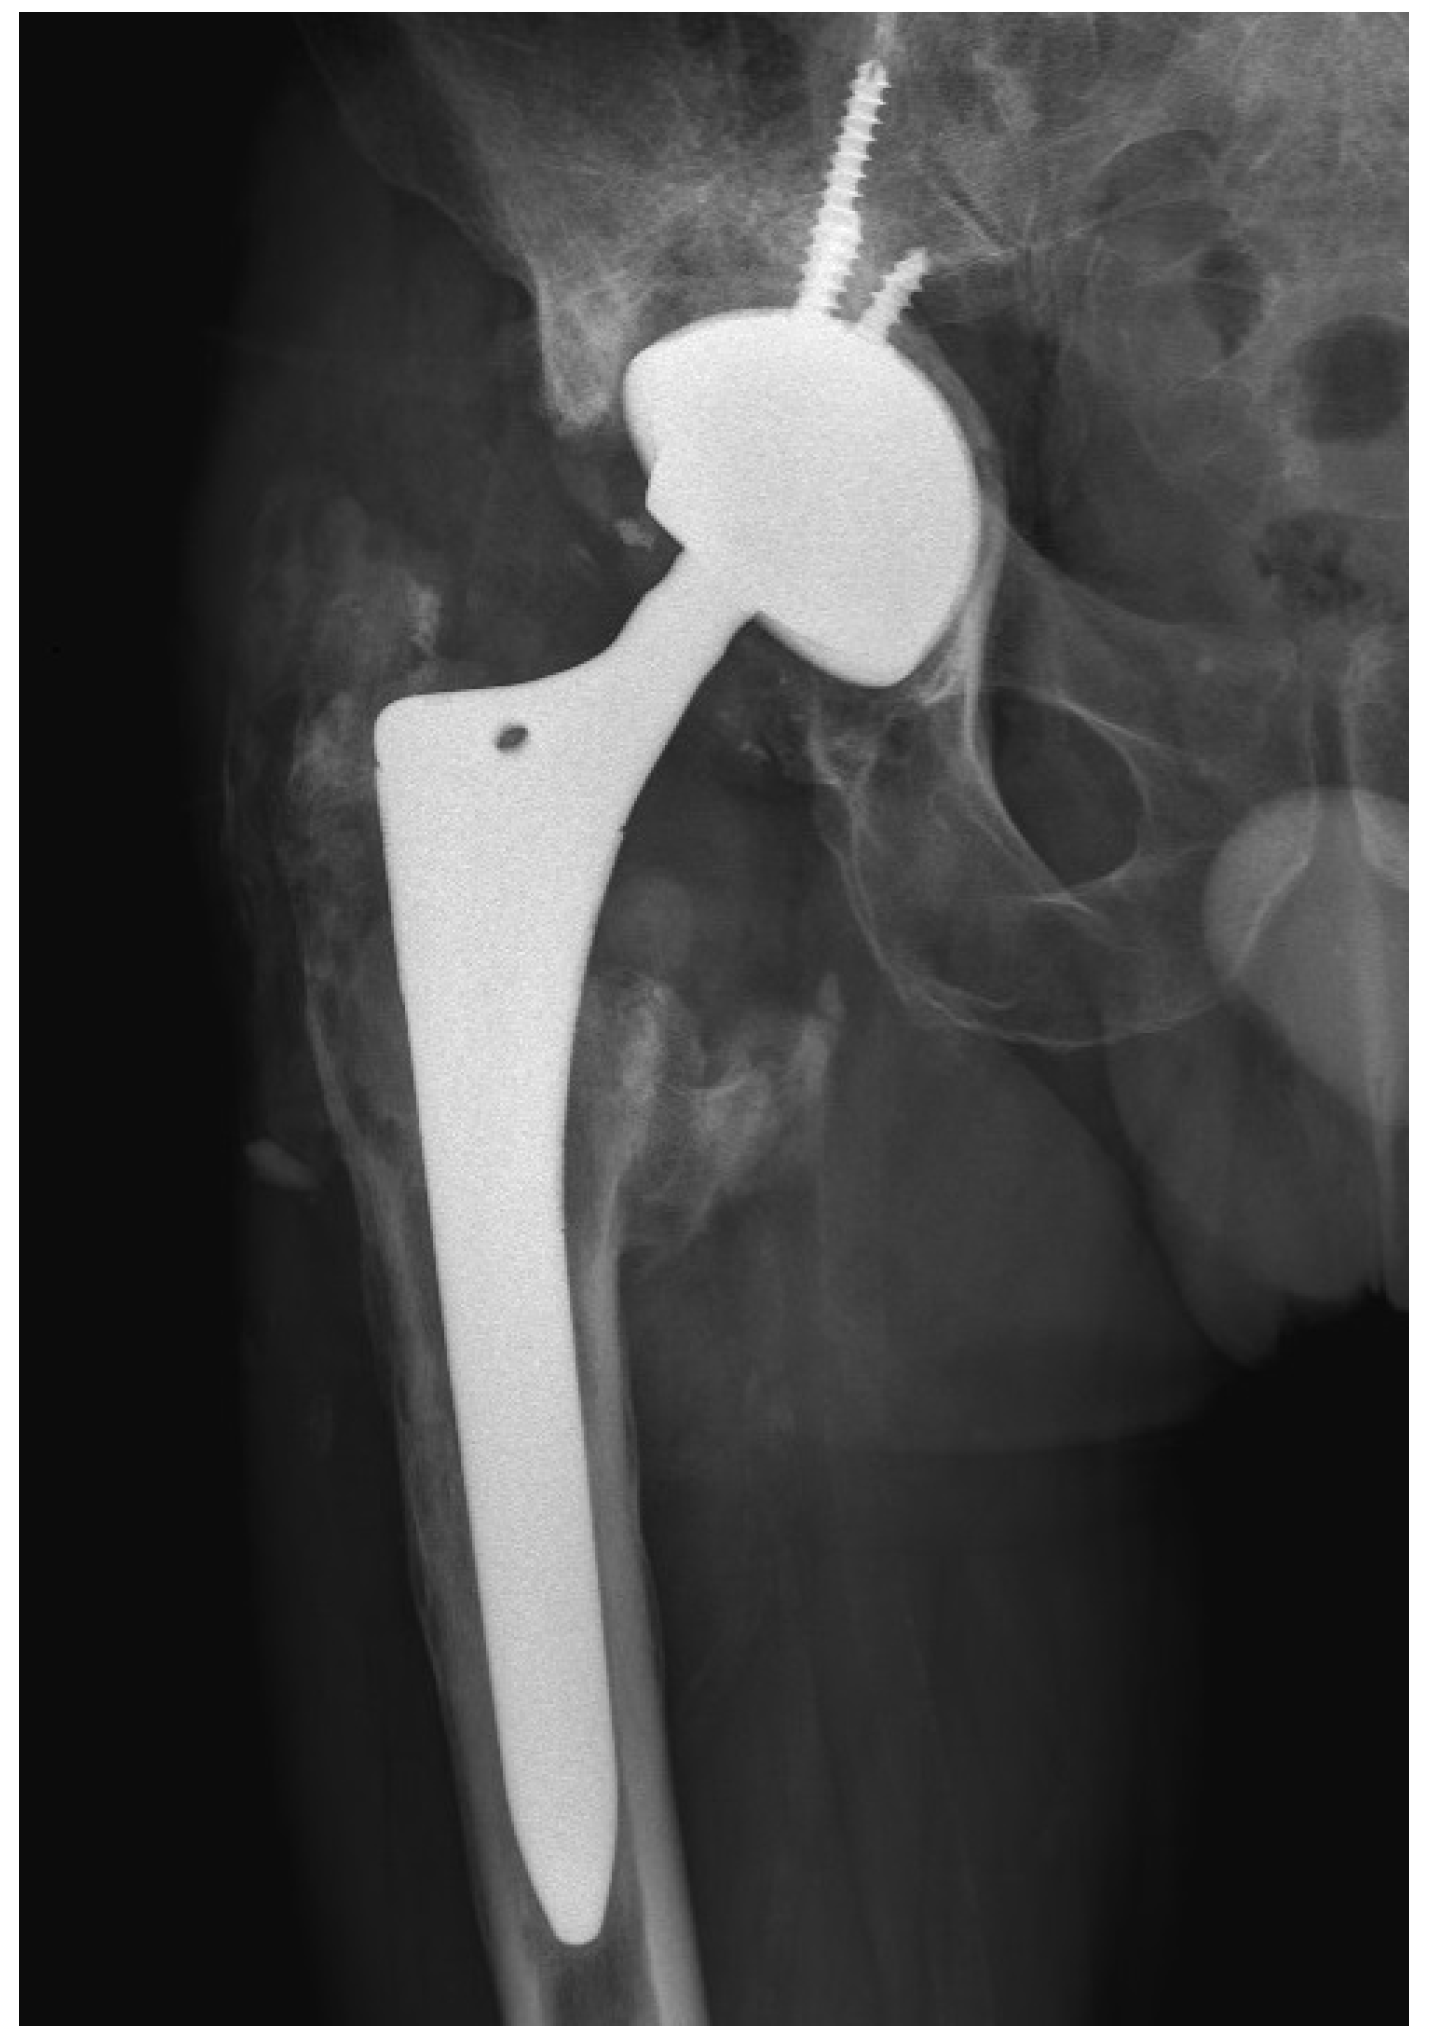

The wound healed uneventfully, and the patient was discharged on the ninth postoperative day. After a 10-day incubation period, all samples were found to be sterile. At the six-month follow-up after the revision THA, the patient reported favorable outcomes. The patient’s HHS was 97 points. Laboratory parameters, including white cell count, hemoglobin level, liver and kidney function, as well as ESR and CRP level, were within normal limits. The radiograph of the patient’s hip depicted stable THA construct without additional osteolysis (Figure 5).

Figure 5. X-ray of the patient’s right hip 6 months after THA revision.